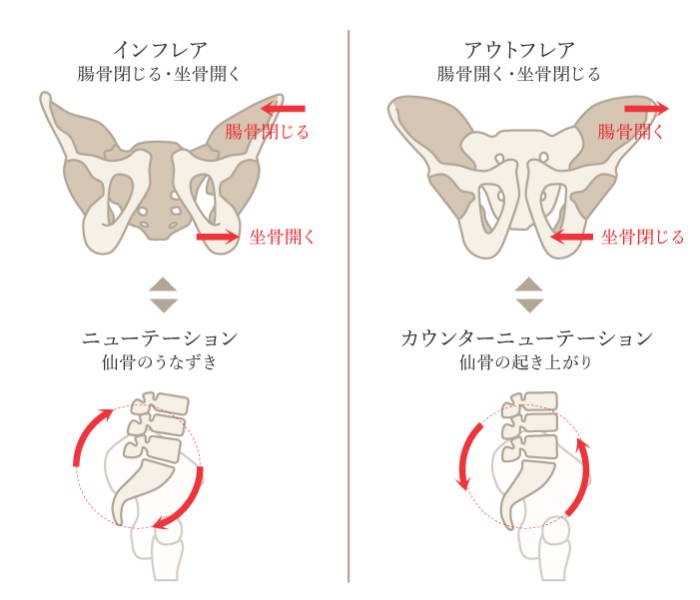

骨盤の機能不全が原因

-

骨盤の仙腸関節から痛みがでる